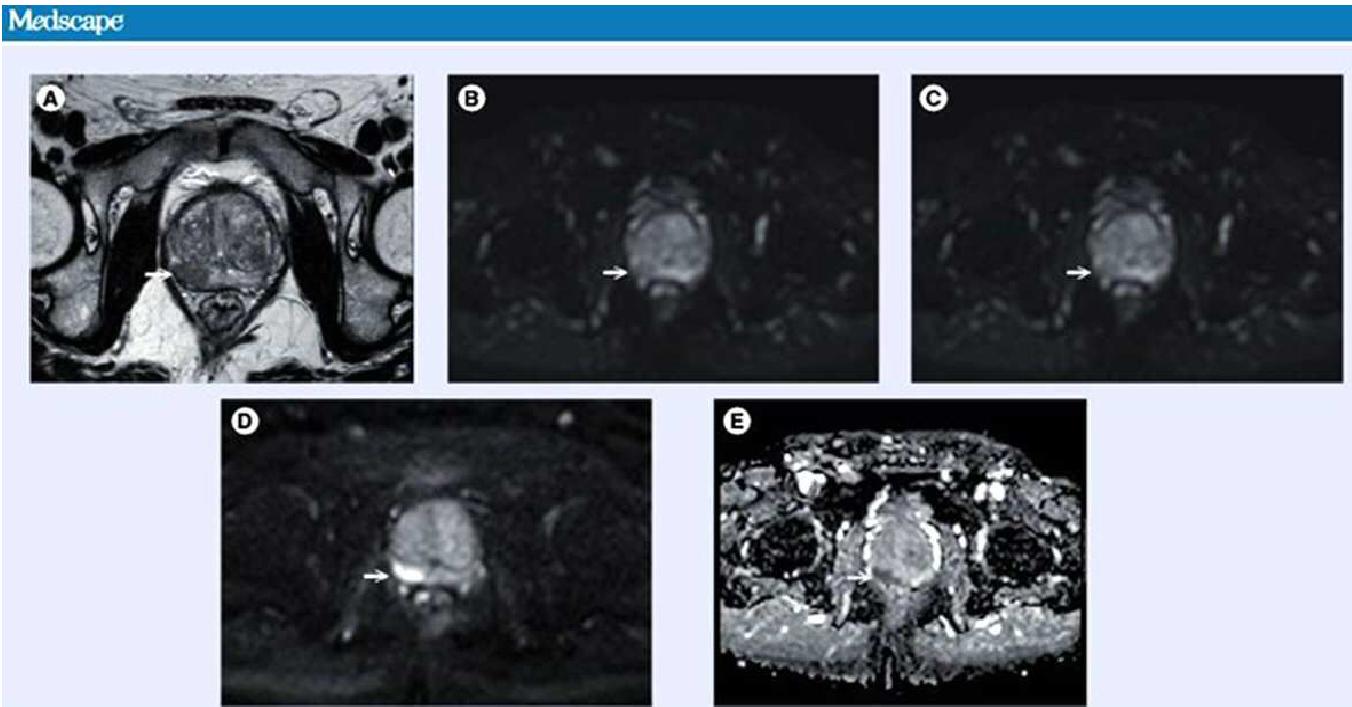

전립선암 진단에 관한 정보제공방법